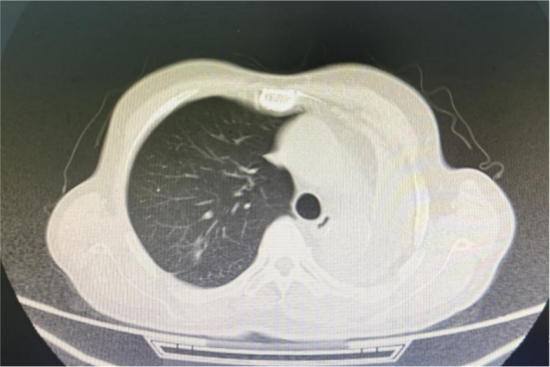

接诊后,李国东主任团队高度重视这位高龄病患,第一时间详细询问患者病史、既往诊疗经过,并完善胸部CT、心肺功能等检查。结果发现:患者20年前因左肺腺癌行肺叶切除术,肺功能显著下降,呼吸储备能力差;同时,病人既往有脑梗病史、糖尿病病史10余年且合并高血压、冠心病,其心肺功能远低于同龄老人。高龄及多种基础疾病相互叠加、肺部手术史致肺功能受损,多重风险让患者的手术治疗陷入两难。

图1.患者肺部CT